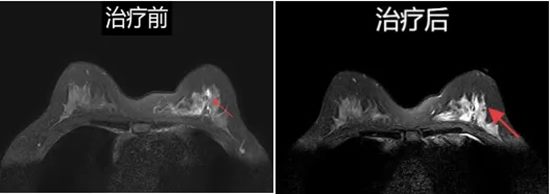

超能力三:追踪治疗反应

无论是化疗还是手术后,乳腺磁共振都能精准评估肿瘤是否缩小或复发,时刻关注病情变化,是医生制定治疗方案的得力助手。